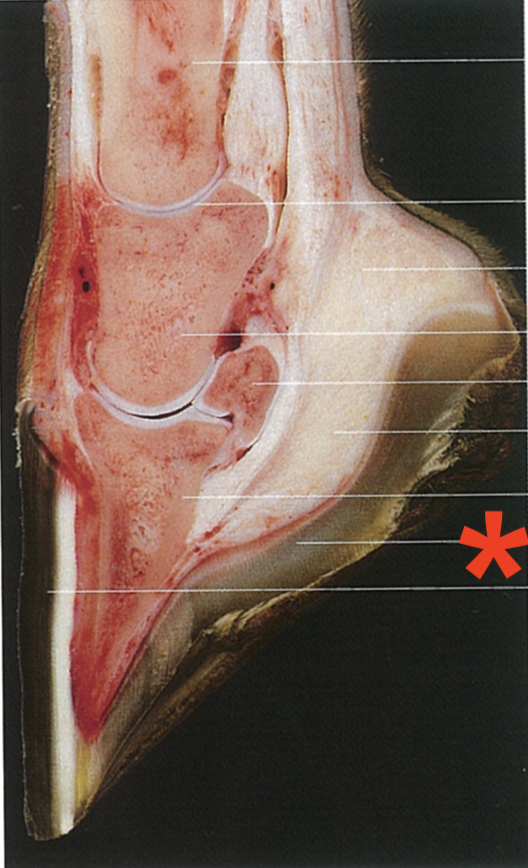

What is shown?

The sole

Digital pad

Frog

Bar

Sole body

Sole crus

Bulb of the heel